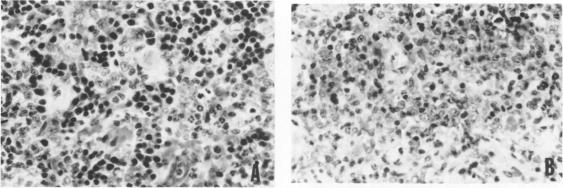

Injection of streptococcus group A cell wall-derived peptidoglycan polysaccharide into a subcutaneous air pouch causes local outpouring of neutrophils and macrophages and distant hemopoietic proliferation in spleen and bone marrow. Cyclosporine A (CyA) suppressed neutrophil accumulation and all cell lines of hemopoiesis. trans-1,2-Bis(5-amidino-2-benzimidazolyl)ethene (BBE) also interfered with neutrophil exudation, yet reduced only the erythroid component of the hemopoietic process. The ethane analogue of BBE, on the other hand, did not prevent neutrophil emigration, but held down splenic erythropoiesis and myelopoiesis. All three compounds stimulated streptococcus group A cell wall-derived peptidoglycan polysaccharide uptake by pouch macrophages. CyA being the least active, BBE and its ethane analogue also produced a shift of wear-and-tear pigment from large numbers of small splenic macro-phages into small numbers of large macrophages. The pouch model is very useful in the study of anti-inflammatory compounds and has furnished the first evidence of CyA interference with massive neutrophilic infiltration and with hemopoietic signals.

将A组链球菌细胞壁衍生的肽聚糖多糖注射到皮下气囊中会导致中性粒细胞和巨噬细胞在局部渗出,并使脾脏和骨髓出现远处造血增殖。环孢素A(CyA)抑制中性粒细胞聚集以及所有造血细胞系。反式-1,2-双(5-脒基-2-苯并咪唑基)乙烯(BBE)也干扰中性粒细胞渗出,但仅减少造血过程中的红系成分。另一方面,BBE的乙烷类似物并未阻止中性粒细胞迁移,但抑制了脾脏的红细胞生成和骨髓生成。这三种化合物均刺激气囊巨噬细胞摄取A组链球菌细胞壁衍生的肽聚糖多糖。CyA活性最低,BBE及其乙烷类似物还使大量小脾脏巨噬细胞中的损耗色素转移到少量大巨噬细胞中。气囊模型在抗炎化合物研究中非常有用,并且提供了CyA干扰大量中性粒细胞浸润和造血信号的首个证据。